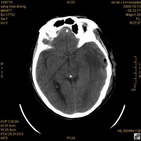

病人杨XX,男,青云街道办事处路踏泉村,住院号51666,CT号:104770。病人因“高血压脑出血”在新泰市人民医院住院治疗5天,治疗效果不佳转入我院,复查CT示左基底节血肿,病人昏迷状态,给予血肿清除术,术后2天复查CT,血肿完全清除,病人恢复好,治疗效果满意。附病人术前术后CT片资料如下。

术前CT

术前CT1 术前CT2 术前CT3 术前CT4